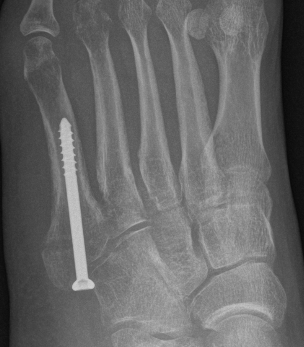

Displaced fracture Nonunion

Screw fixation Zone 2 nonunion

Screw fixation Zone 3 nonunion